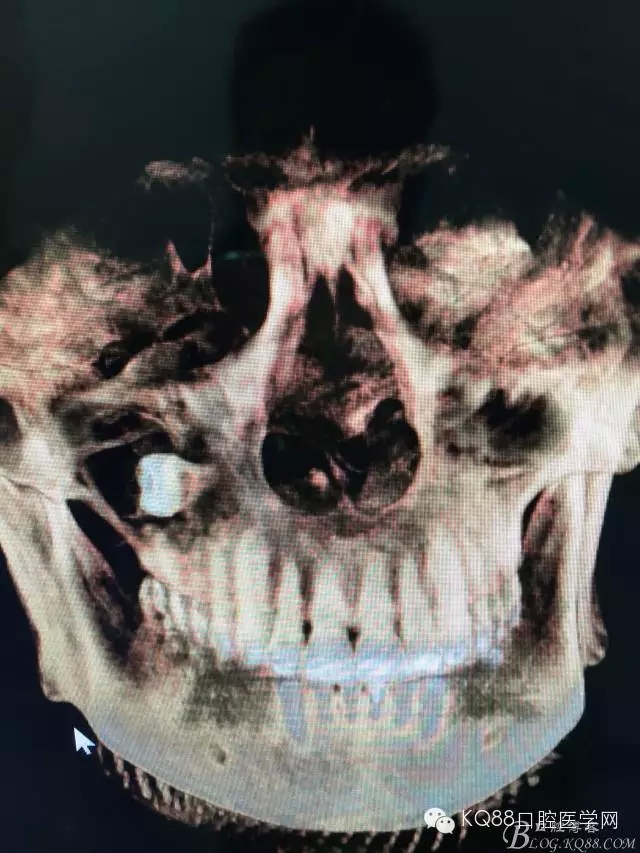

圖4.三維重建影像顯示:18牙體位于上頜竇內(nèi)。其上頜竇頰側(cè)骨壁破壞消失。左側(cè)骨壁完好無缺。